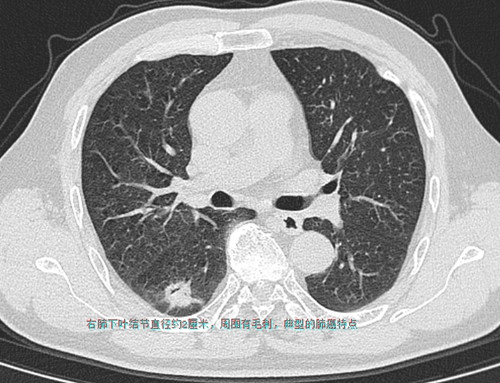

66岁的周嗲嗲家住马王堆,因气促咳嗽在捷克论坛 呼吸五科住院,胸部CT检查发现在右肺下叶有一个约鹌鹑蛋大小结节,同时在纵膈发现一巨大肿物压迫气管引起狭窄,经胸外科会诊,右肺下叶结节肺癌的可能性非常大,纵膈肿物是颈部甲状腺肿瘤往胸腔内长压迫气管,两个问题都要手术治疗。

2022年1月4日,新开科的胸外二科在周亚夫主任的带领下,开展了首台单孔胸腔镜右肺下叶癌根治术+胸骨后巨大甲状腺肿切除术,一次手术解决了两大问题,不仅为患者节省了费用,还减少了两次麻醉、手术带来的风险和并发症。